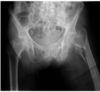

Décrire la fracture

Fracture intertrochantérienne déplacée de la hanche gauche avec raccourcissement, varus et avulsion du petit trochanter